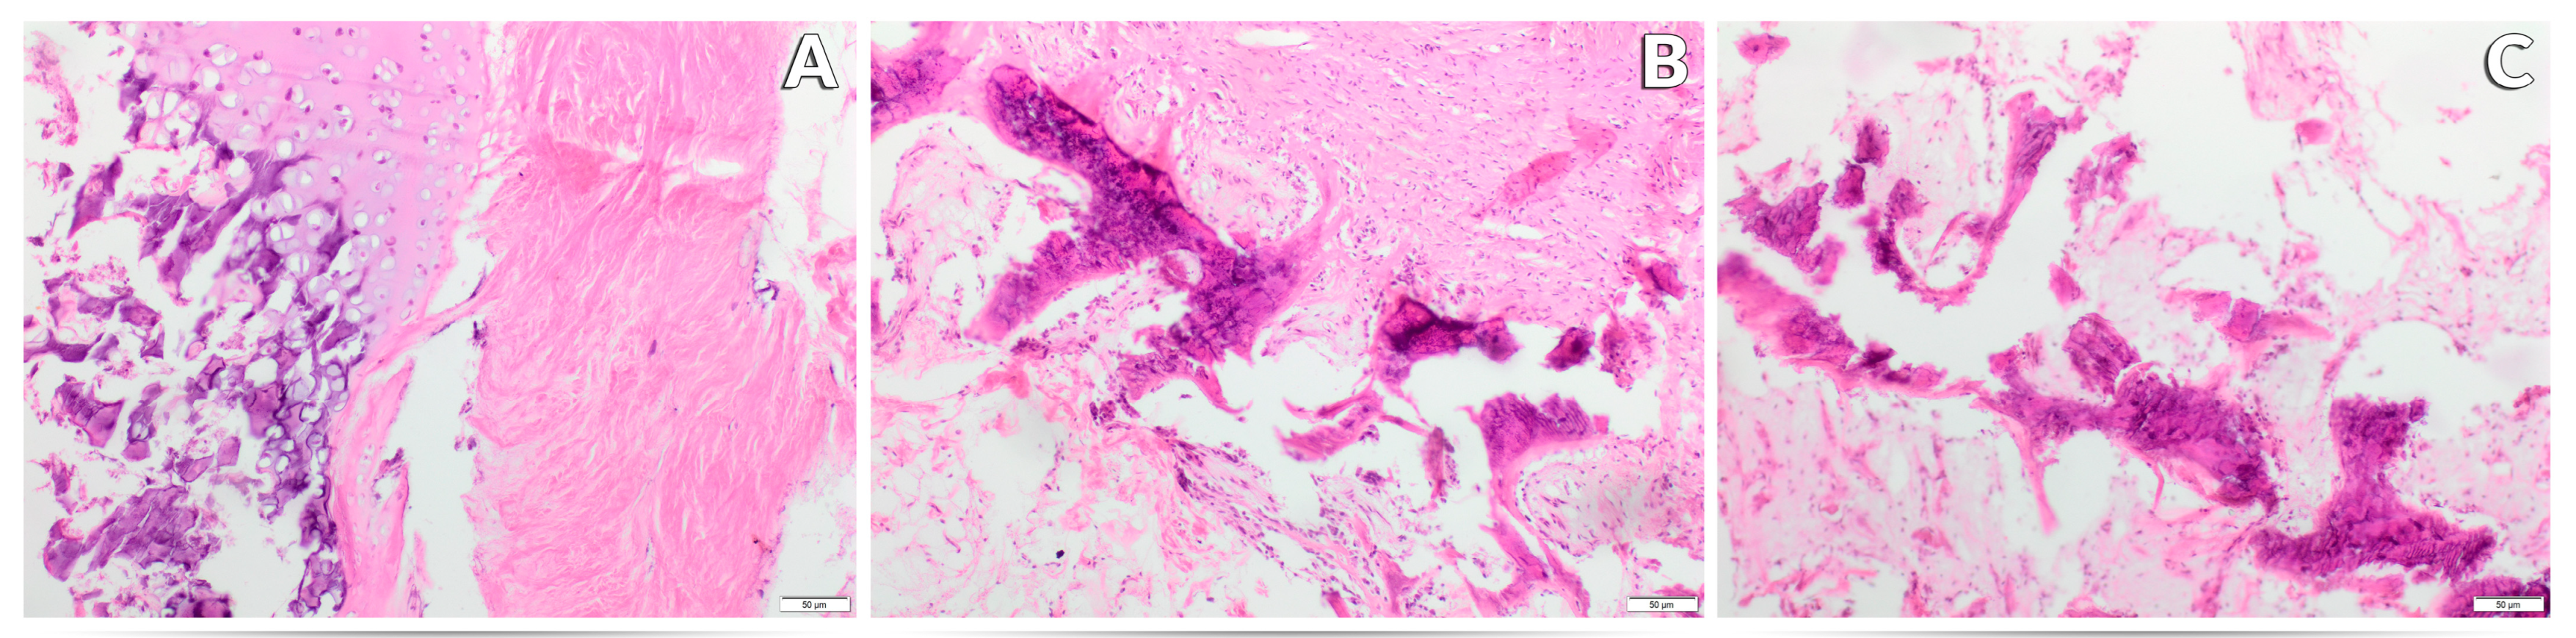

3.3. Effect of Experimental Factors on the Histological Image of the Femur